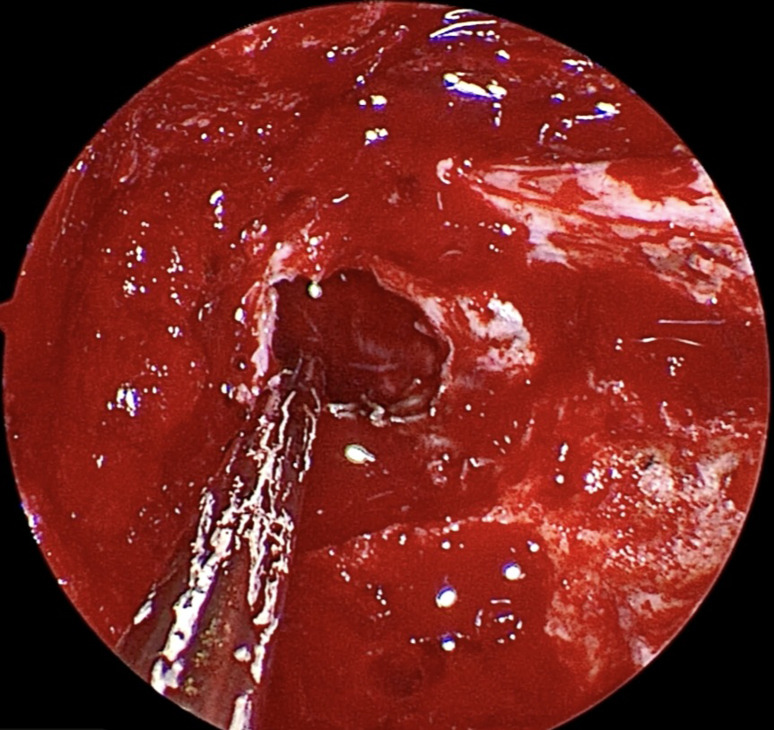

Endoscopic endonasal transsphenoidal approach of pituitary macroadenoma and optic canal stenosis in a patient with McCune-Albright syndrome.

Abstract Image